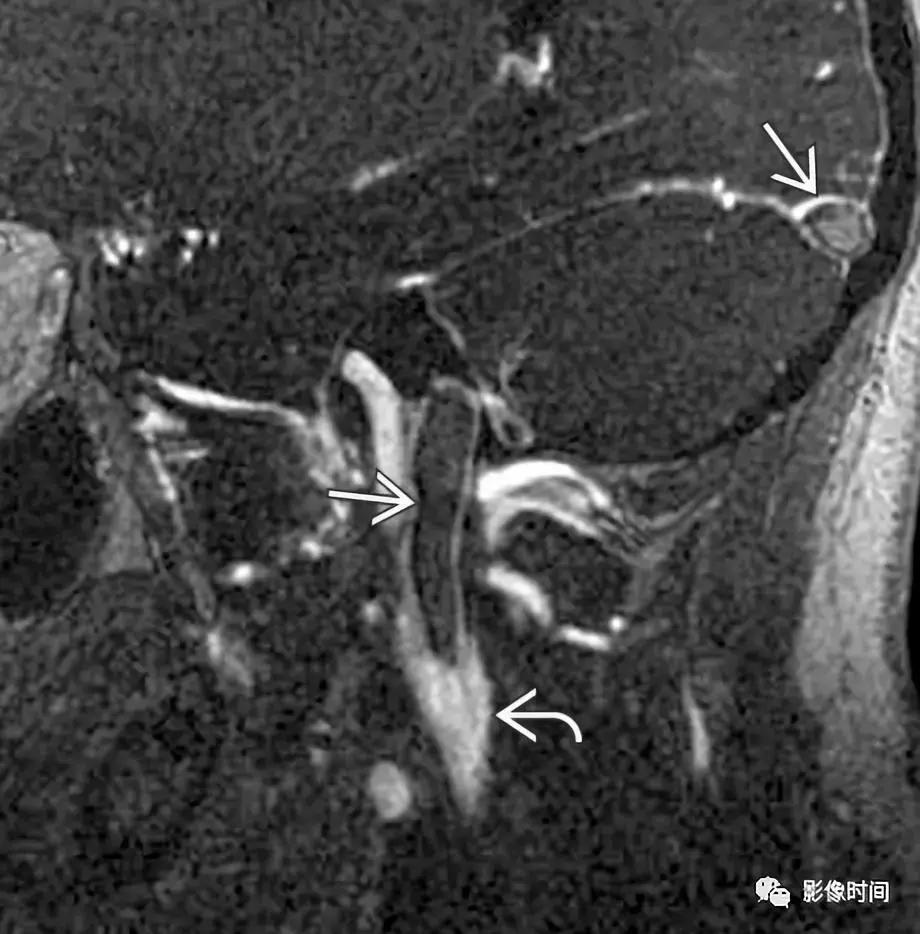

CTA 显示轴向左侧颈总动脉分叉区周围软组织增厚(无尾箭头),管腔未见狭窄,可见软斑块(长箭头)。TOFMRA 显示左颈内动脉周围软组织增厚,注意右颈内动脉的正常外观。冠状 T1WI+C 显示左侧颈内动脉周围明显强化 (长箭头),注意右颈内动脉的正常外观。激素治疗随访约 4 个月后,冠状 T1WI+C 显示颈内动脉周围厚度减轻。